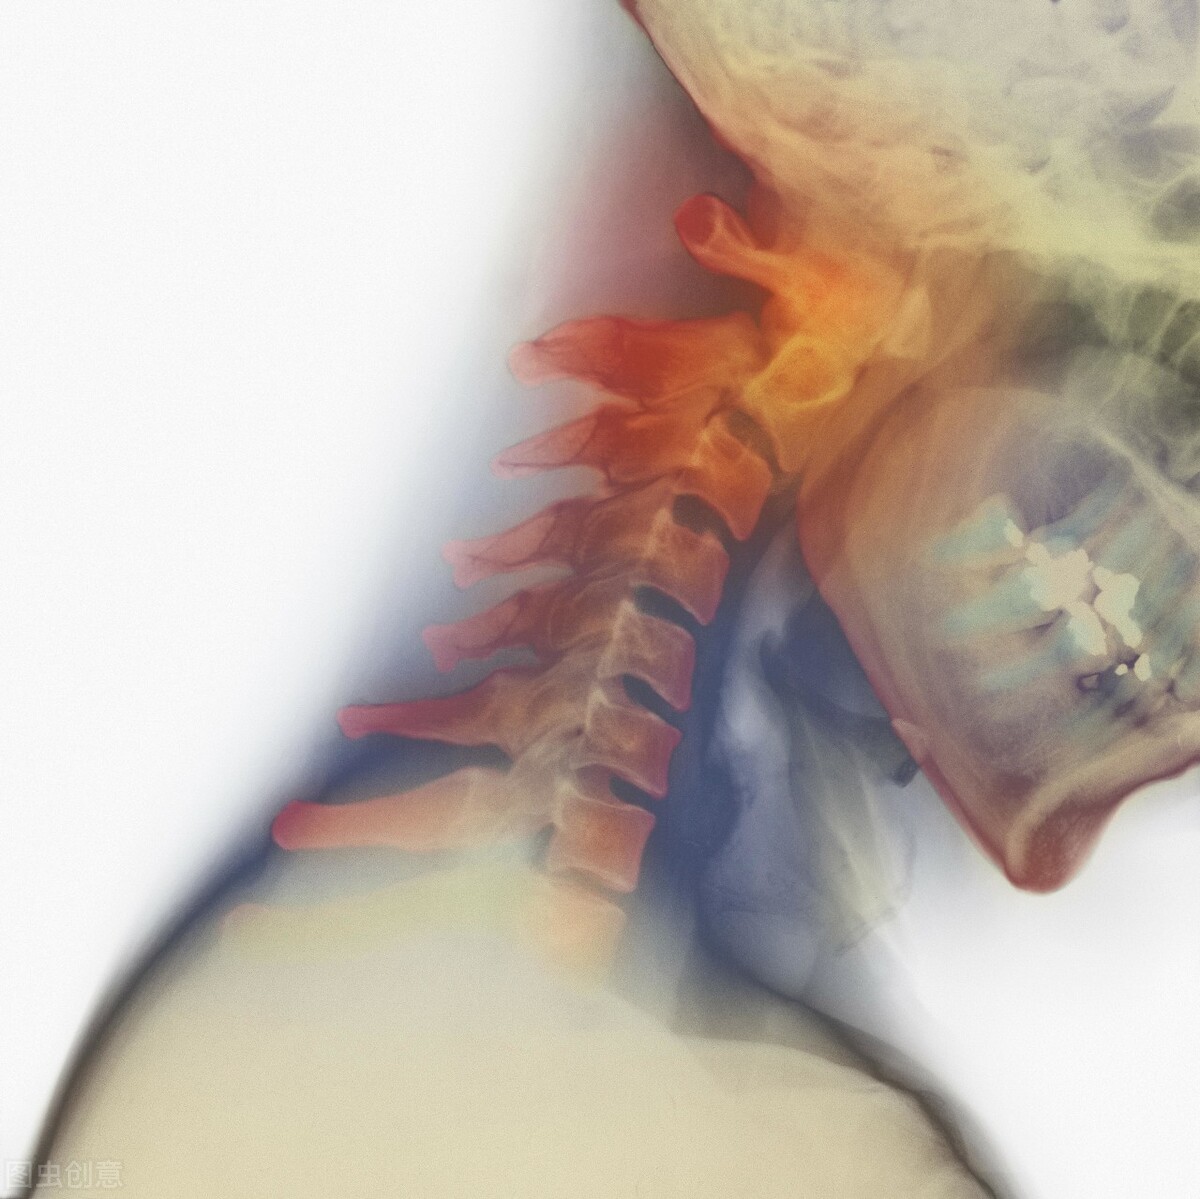

马师傅的脑供血不足和冠心病已有二十多年的历史。起初,他只是长时间阅读或伏案工作时,会感到头晕眼花和脖子僵硬,稍作休息便能缓解。然而,随着时间的推移,情况逐渐恶化,症状变得越来越严重,看东西变得模糊不清,头部昏沉,伴有心慌、胸闷和恶心。睡眠质量下降,生活和工作都受到了极大的影响,让他痛苦不已。

1926年,专家们就已经对交感型颈椎病进行了研究并进行了报道。这种病是由颈椎间盘的退化、颈部软组织的损伤等多种因素引起的,会导致颈椎周围的交感神经末梢受到刺激,从而引发自主神经功能的紊乱。其临床症状多样,但客观体征较少,患者可能会出现交感神经的兴奋或抑制症状,同时常常伴随有椎基底动脉供血不足的情况。